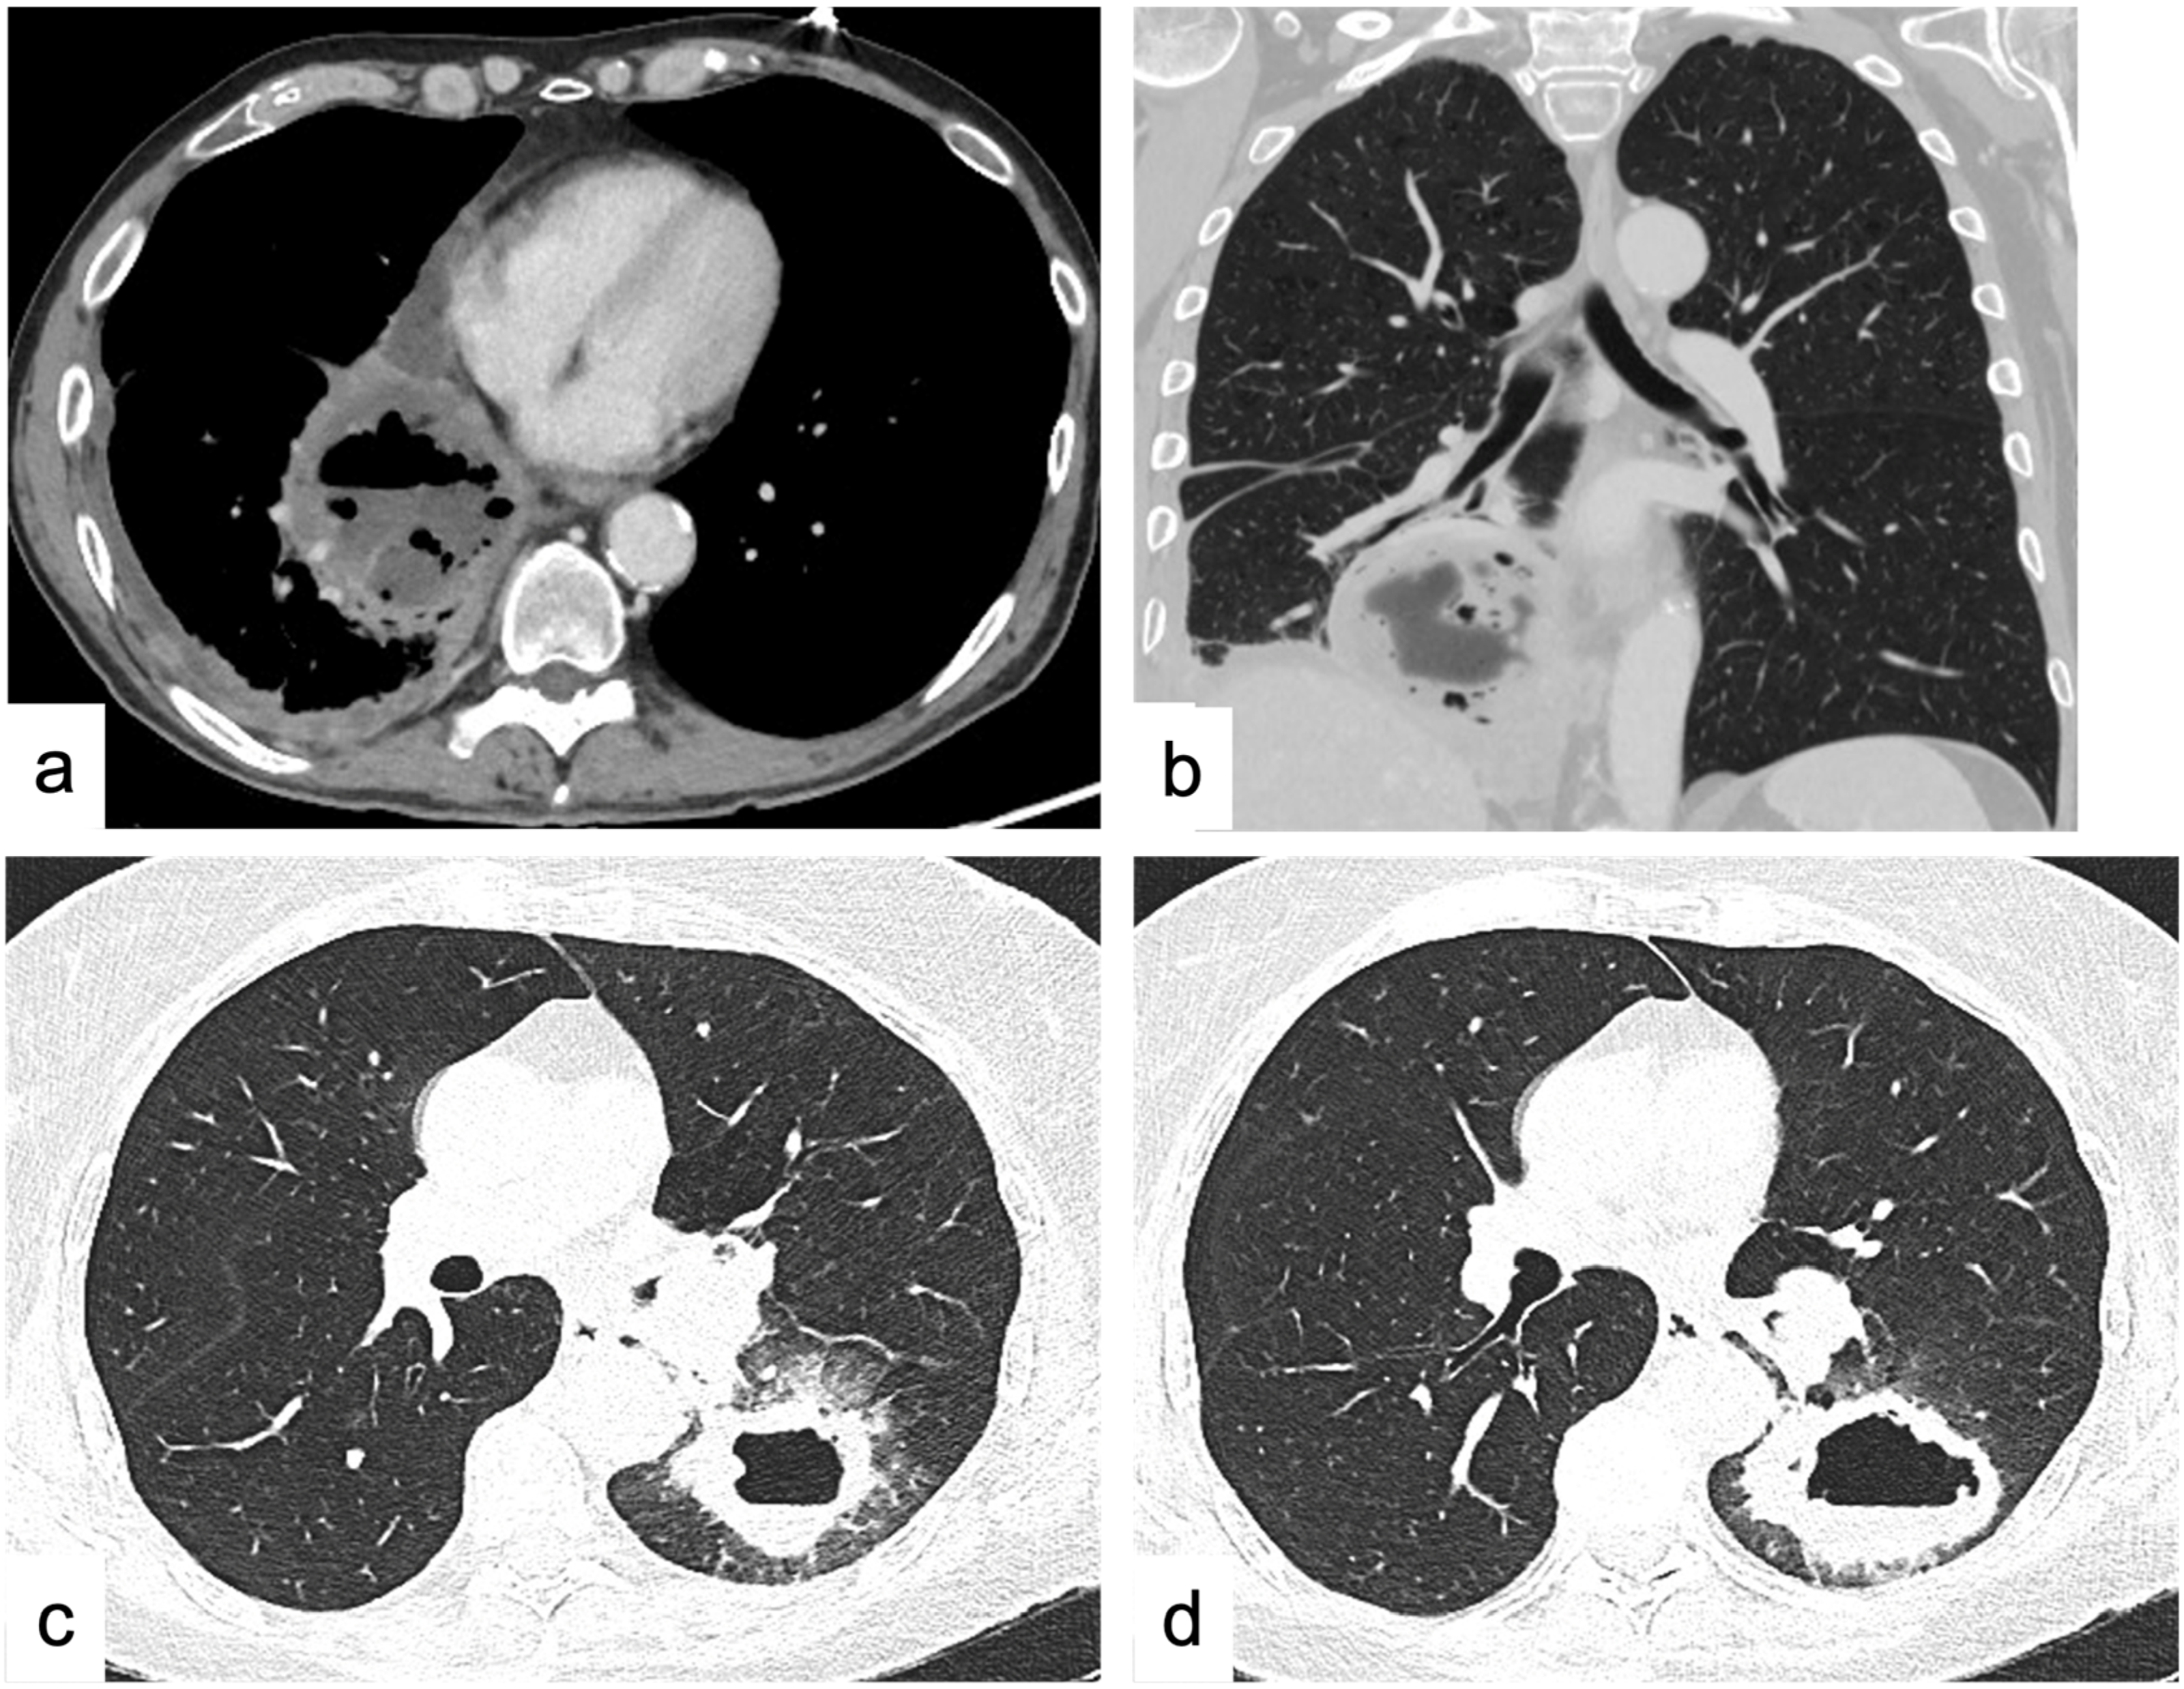

4.1.6. Cavitations and Cysts

4.2. Diffuse Lung Disease

Consolidations